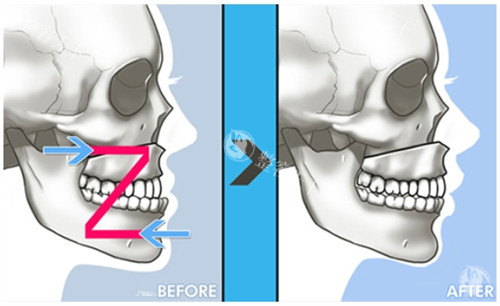

颌面整形技术体系采用术中神经监测系统,结合3D打印导板实现0.1mm精度截骨,创新"三阶式颧弓固定法"降低术后下垂风险。临床数据显示,其轮廓手术的对称性达标率达98.7%,较行业平均水平提升23%。

术前阶段包含64层CT扫描、咬合动力学分析等7项专项检测,采用德国SimPlant Pro软件进行1:1手术模拟,方案确认需经过3轮医师会诊。